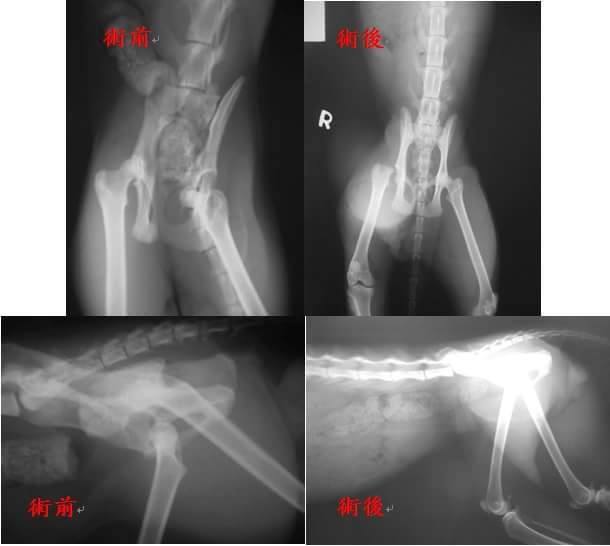

吉吉身上有輕微外傷但有脫水及眼鼻分泌物,初步驗血發現肝指數及白血球都有偏高,有發炎現象,貓二合一檢驗都為陰性,後腳經X光檢查發現有右側骨盆骨折,造成股骨頭及骨盆內凹,促使骨盆直腸通道變小,有可能會造成日後排便問題且內凹的股骨頭會造成疼痛及行走受限,建議股骨頭切除,目前已先點滴及給藥治療,後續如狀況穩定後才考慮進行手術。

9/5吉吉持續點滴、氣霧治療中,9/7吉吉點滴打到手腫脹醫生先幫拔點滴,休息一下,9/10 醫師再次幫吉吉血檢,且評估眼鼻分泌物明顯改善,於9/11進行結紮與股骨頭切除手術。

4.X光檢驗 400×2=800

9.股骨頭摘除手術(9/11) 6000